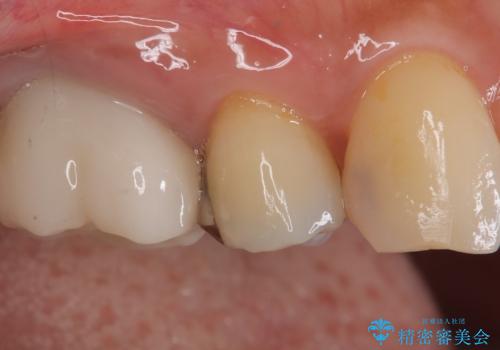

- 定期検診にてむし歯が見つかった患者さまです。

金属アレルギー体質とのことで、セラミックインレーにて修復治療を希望されました。

見た目も良く、満足していただきました。